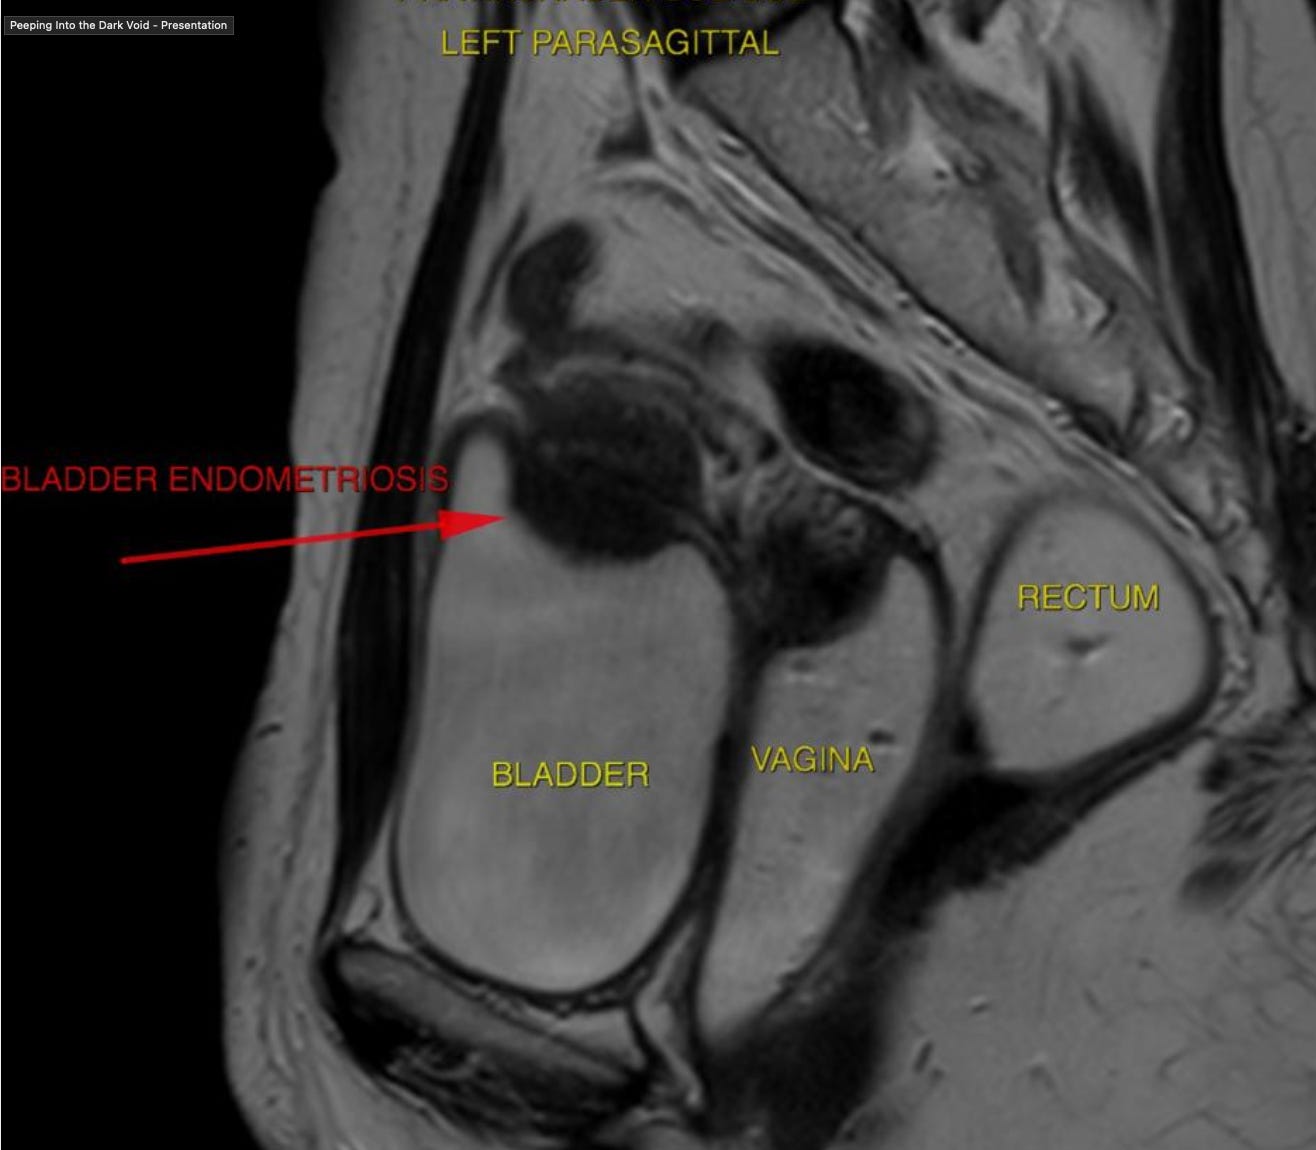

Bladder Endometriosis shows up in the anterior compartment in our MRI

When involved, it looks something like this